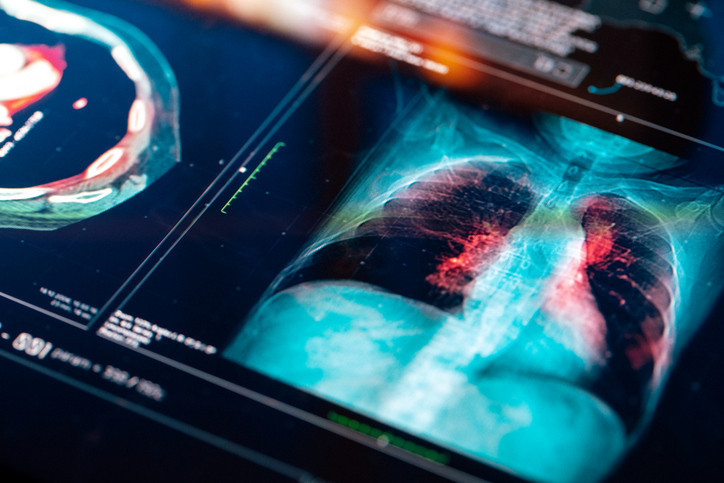

Zatürre, akciğerlerdeki küçük hava keseciklerini etkileyen bir göğüs enfeksiyonu olarak tanımlanıyor. Hastalar nefes almakta zorlanabilir, bazı durumlarda kan öksürebilir veya solunum cihazına bağlı olarak yaşam mücadelesi verebilirler. İngiltere ve Galler’de 2024 yılında 23.061 kişinin yaşamını yitirdiği istatistiklerde, zatürre ve grip birlikte ölüme neden olan en önemli faktörler arasında gösteriliyor.

Hunter, grip virüsünün üst solunum yollarına saldırarak, bu bölgedeki mikroskobik tüyler olan siliyalara zarar verdiğini ifade etti. Bu tüyler, akciğerlerdeki alveol adı verilen hassas hava ceplerine yerleşen bakterileri ve zararlı parçacıkları uzaklaştırmakla görevlidir. Siliyalara zarar gelmesiyle akciğerler bakterilere karşı savunmasız hale gelir. Alveoller enfekte olduğunda sıvı, kan veya irinle dolar ve oksijenin kan dolaşımına geçmesi neredeyse imkânsız hale gelir.